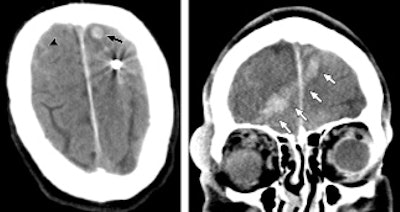

Of the 40 patients received by BWH, 31 (78%) underwent diagnostic imaging. A total of 149 imaging scans were ordered, with x-ray accounting for the bulk of the exams (119, or 80%), followed by CT (30, or 20%). There were no emergency department orders for MRI or ultrasound.

Of the scans ordered, 57 x-ray studies were completed on 30 patients and 16 CT scans were performed on seven patients. Because several orders were for multipart CT examinations, this corresponded to 28 unique CT exams performed on seven patients.